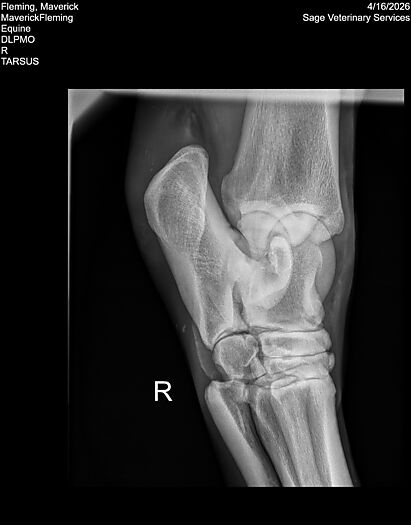

**Maverick sells at the Colorado Horse Sale’s Best of the West Select Sale on May 30th in Castle Rock, CO - He will complete the riding & handling Sift Exam, baseline veterinary exam, and will sell with 4 total radiographs (DLPMO & Front Foot Lateral)**